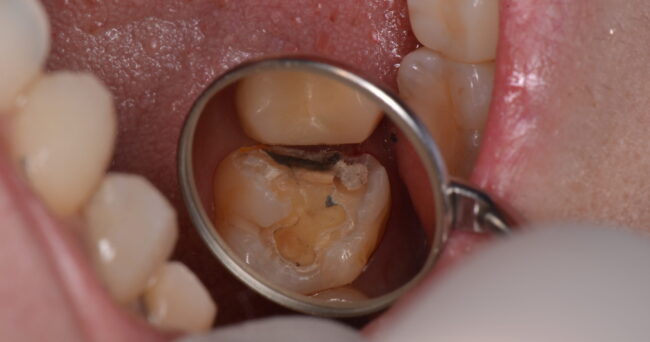

まずは下準備、治療する歯のむし歯をとります

大きな虫歯がありました。まずは症状がないことを確認します。症状があれば、神経をとる治療をしていきます。ここの歯の状態を確認する間に、反対側の歯の治療も行いました。

なぜ、こんなに大きいのか(・_・;)上下とも症状がないことを確認したのち、どちらも範囲が広いため、クラウンという、全周を覆う治療を提案しました。その後、セラミックスでの治療を希望されたので、処置に入りました。